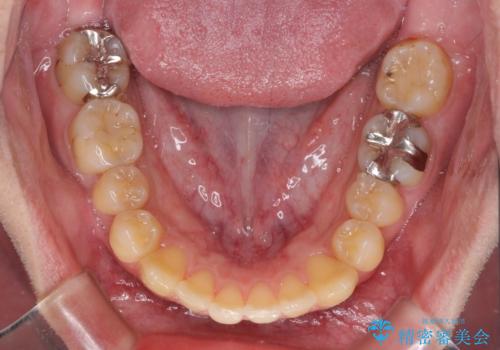

前歯のクロスバイトをインビザラインで矯正治療

- 前歯のデコボコとクロスバイトを気にして来院された患者様です。

前歯を早く整えたいとの希望があったので、ワイヤー矯正にて短期間でクロスバイトを解消し、その後インビザラインにて整えることとしました。